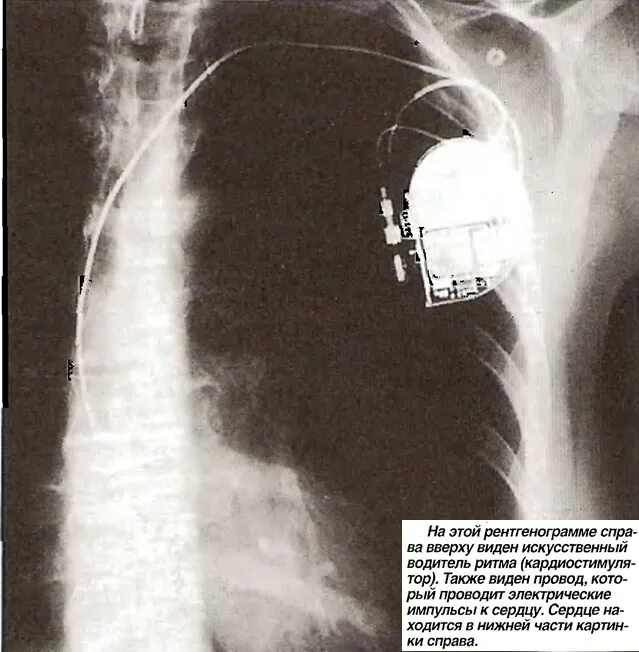

Искусственный водитель ритма